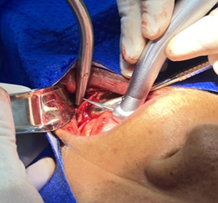

Luego se realiza un acceso quirúrgico con un bisturí y una hoja #15, haciendo una incisión en la encía muy cerca del área del reborde donde se va a remodelar, la ubicación y la longitud va a depender de la extensión de las irregularidades que tuvo el paciente, en este caso fue una incisión a lo largo de toda la parte anterior en el área de canino a canino, luego se separa la encía suavemente con el periostótomo para lograr la exposición del hueso subyacente, para llegar a la parte primordial que es la remodelación ósea (Figura 4).

Figura 4. Procedimiento quirúrgico.

Elaboración: Los autores.